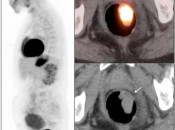

After the stomach, normal intense colon uptake is the most over-called “abnormality” by the inexperienced PET/CT radiologist.

The colon — focally or diffusely — often demonstrates intensely uptake of FDG.

Proposed mechanisms for colonic uptake of FDG include muscle contractions, the presence of lymphoid tissue and intraluminal contents.

The most common sites of normal physiologic intense colon uptake are the cecum and the distal rectum.

Generally, colonic uptake should be considered normal unless:

- There is an accompanying CT abnormality (e.g. focal bowel wall thickening or focal mass); or

- A solitary focus of intense uptake presents in an otherwise non-avid (or minimally avid) colon. Although this focal uptake may still represent normal physiologic uptake, it is reasonable to raise the possibility of a small polyp and recommend colonoscopy (polyps are rarely visible on the CT images).

We generally report, “As an adenomatous polyp or other pathology cannot be excluded, further evaluation with colonoscopy may be warranted, if not recently performed.”

Caveats:

Hemorrhoidal Inflammation:

Focal intense uptake in the ano-rectal region is a very common finding. It is considered normal in the absence of an associated soft tissue abnormality. It is often attributed to hemorrhoidal inflammation.

Be careful to not confuse ano-rectal uptake (typically representing hemorrhoidal inflammation) with rectal uptake (often malignancy).